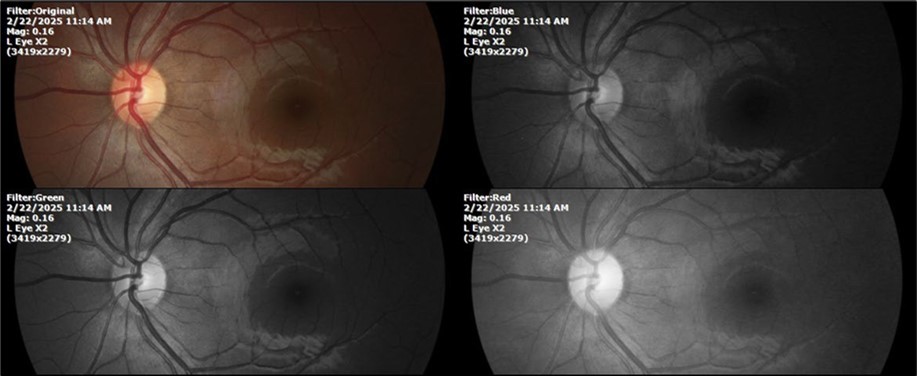

Figure 23.The mirror reflection of the left eye, without anomalies.

Figure 24.The eye that was not affected by the trauma (left side) remains in good condition.

Figure 28.The photograph of the left eye shows a specular reflection without pathology data.

Figure 29.The transparent media of the left eye does not show any alteration.

Figure 30.The anatomy of the posterior pole of the left eye is preserved, without showing pathology data.

Figure 34.The mirror reflection of the healthy eye (L. E.) continues within normal limits.

Figure 35.The anatomy of the anterior segment of the left eye is shown without alterations.

Figure 36.The retina, optic nerve, choroid, and macula of the left eye do not show any evidence of sympathetic ophthalmia.